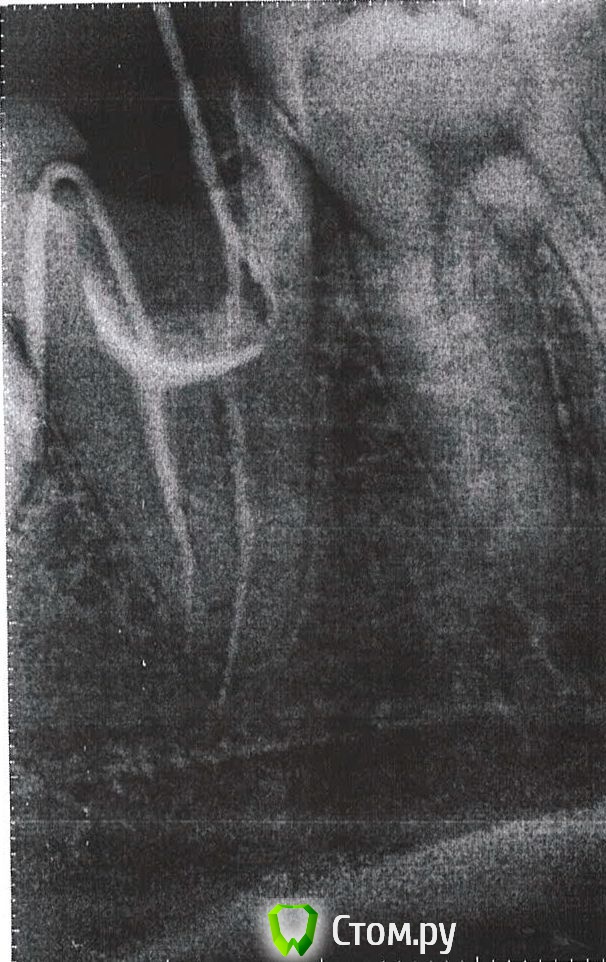

FJoe Опубликовано 24 августа, 2014 Автор Поделиться Опубликовано 24 августа, 2014 (изменено) 4.7 профоткать, подозрение на выведение Оно там есть, скорее всегоhttp://forum.stom.ru/topic/26608-lechenie-pulpita-chistka-kanalov/ Это снимок в процессе, итоговый будет позже Изменено 24 августа, 2014 пользователем FJoe Ссылка на комментарий

FJoe Опубликовано 25 сентября, 2014 Автор Поделиться Опубликовано 25 сентября, 2014 (изменено) 47 через месяц после лечения каналов. Изменено 25 сентября, 2014 пользователем FJoe Ссылка на комментарий